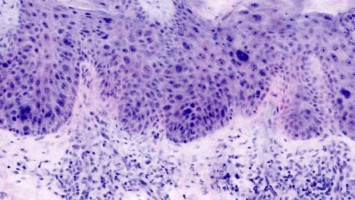

Update zur Pathologie der Peniskarzinome

Die Inzidenz von Peniskarzinomen beträgt in Europa < 1 %. Etwa die Hälfte der Peniskarzinome entsteht über die Präkanzerose hochgradige squamöse intraepitheliale Läsion (HSIL) durch eine transformierende Infektion mit humanen Papillomaviren (HPV) …

Titelbild Kongress Kompakt EULAR 2025/© Hintergrundbild: william87 / stock.adobe.com, Wunde wird mit Wundspray versorgt/© Ilja / Stock.adobe.com (Symbolbild mit Fotomodell), Kutane Arzneimittelreaktion/© Hötzenecker, W., Hautveränderungen an der rechten Wange/© M.V. Heppt, In Risikogebieten tragen circa 1–2 % der Zecken das FSME-Virus./© astendal / stock.adobe.com (Symbolbild mit Fotomodell), MRT-Aufnahmen der Kopfschwarte bei Riesenzellarteriitis/© Universitätsklinikum Würzburg, Fillerbehandlung im Gesicht eines Mannes/© Microgen / stock.adobe.com (Symbolbild mit Fotomodell), Neurofibromatose auf der Haut/© Alexander Schuh / Klinikum Fichtelgebirge, Wespen auf Stein/© merlion / Getty Images / iStock (Symbolbild), Eine Person raucht eine E-Zigarette/© vchalup / stock.adobe.com (Symbolbild mit Fotomodell), Mund mit herausgestreckter Zunge: Medikamenteninduzierte Xerostomie mit extrem trockener Mundschleimhaut/© F. Halling | Die junge Zahnmedizin (16)·3:26-31, Aknenarben/© Hautwerk, Konfokale optische Kohärenztomographie mit Line-Field-Technologie/© Deußing, M. et al. / all rights reserved Springer Medizin Verlag GmbH, Ex vivo konfokales Laserscanmikroskopiebild eines Morbus Bowen/© Grunewald S et al. / all rights reserved Springer Medizin Verlag GmbH, Zwei Injektionspens mit Semaglutid/© Kassandra / Stock.adobe.com, Immuncheckpointinhibitoren binden an Krebszelloberflächenproteine /© Juan Gärtner / stock.adobe.com, Morbus Castleman: Sonographie eines Lymphknotens/© Springer Medizin, Person kratzt sich am Arm/© 9nong / stock.adobe.com (Symbolbild mit Fotomodell), Arzt tastet Bein ab/© Stratocaster / Stock.adobe.com (Symbolbild mit Fotomodellen), Hämorrhagisches Erysipel am Unterschenkel/© Sunderkötter C et al. / all rights reserved Springer Medizin Verlag GmbH, Piks in Oberarm/© stalnyk / stock.adobe.com, Gewitter mit Blitzschlag/© solarseven / Getty images / iStock, Behandlung eines diabetischen Druckulkus/© Alexander Schuh, Eine Person, die sich juckt und kratzt/© Maria Fuchs / stock.adobe.com (Symbolbild mit Fotomodell), Die Leitlinien für Ärztinnen und Ärzte, Herpes Zoster am Rücken/© Mumemories / Getty Images / iStock (Symbolbild mit Fotomodell), Mann erhält einen CT-Scan /© Mark Kostich / stock.adobe.com (Symbolbild mit Fotomodell), DGIM Podcast-Reihe - Frailty/© (M) David L / peopleimages.com / Stock.adobe.com (Symbolbild mit Fotomodell)